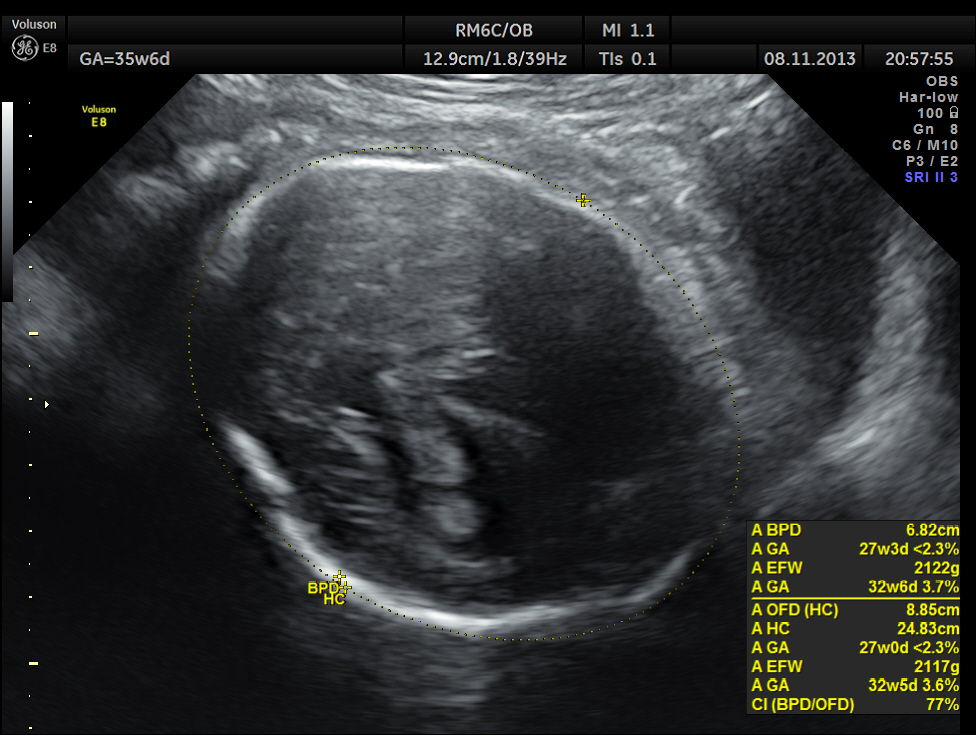

The scan was repeated at 36 weeks of gestation.

BPD, HC show < 2.3 % tile.

AC and FL appear to be normal.